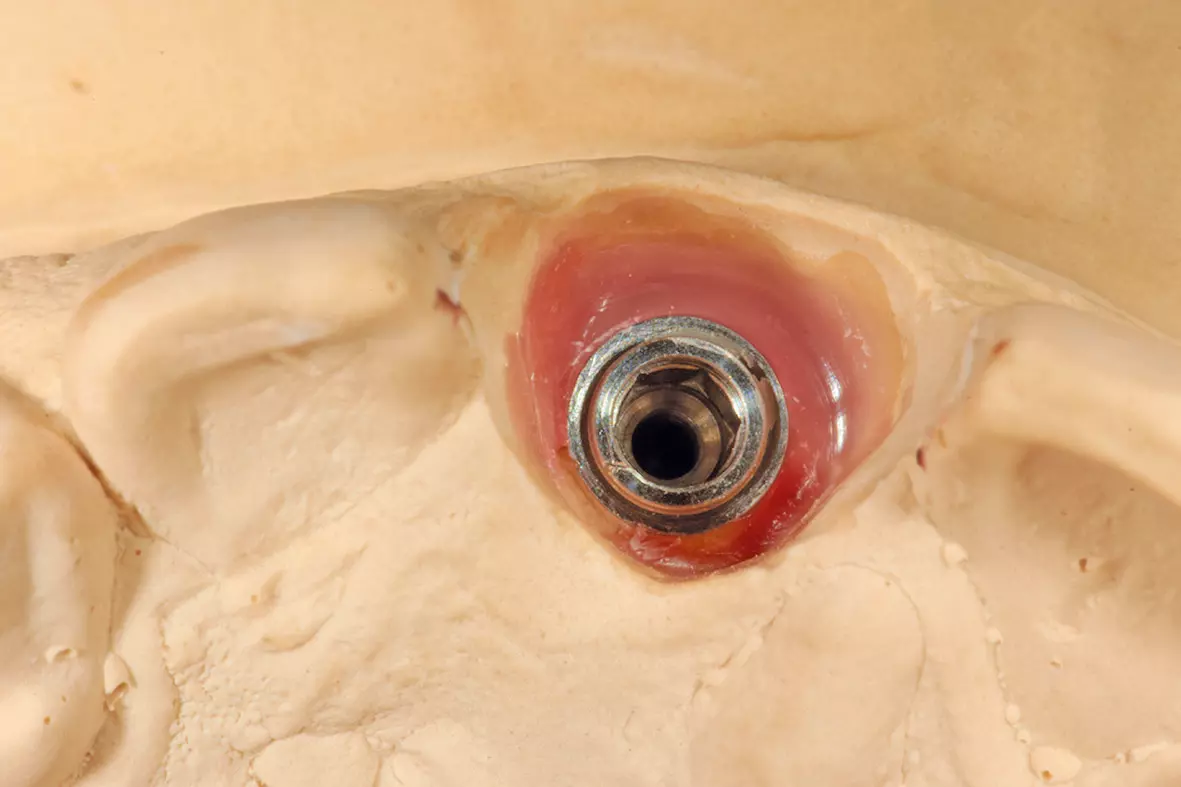

Nach einer Einheilphase von drei Monaten konnte implantiert werden. Es sollte eine okklusal verschraubte Krone verwendet werden. Die Entscheidung des Implantatsystems fiel auf ein ELEMENT Implantat von Thommen Medical, da es über einen sehr kleinen Schraubenkanal verfügt und damit eine gute prothetische Versorgung – gerade im Frontzahnbereich – ermöglicht. Hier hat man es häufig mit Problemen der Einschubrichtung des Implantates zu tun und ein kleiner Schraubendurchmesser schafft Platz, um eine Verschraubung möglich zu machen. Für die Implantation erfolgte in Lokalanästhesie eine krestale, leicht lingual versetzte Schnittführung unter Erhaltung eines einige Millimeter breiten Streifens befestigter Mukosa. Das Implantat wurde in korrekter Position ca. 3-4 mm oberhalb der Schmelz-Zement-Grenze sowie ca. 2 mm oral von der Verbindungslinie der benachbarten Wurzeloberflächen und mit einer Implantatachse palatinal von der geplanten Schneidekante gesetzt (Abb. 7 und 8). Danach wurde ein steriler Abformpfosten für eine offene Abformung aufgeschraubt. Zur Anfertigung des Index wurde Triad Gel (Triad Gel Clear Colorless, Dentsply International, York, PA, USA) benutzt. Dazu wurde das Material in eine sterile 2-ml-Einmal-Spritze gefüllt und auf den Abformpfosten und beide Nachbarzähne aufgetragen. Die Aushärtung erfolgte mit einer in eine sterile Folie eingepackten Polymerisationslampe.

Man konnte erkennen, dass durch die sorgfältige Vorbereitung des Implantatbettes das Implantat exakt an der Stelle stand, an der vorher die Zahnwurzel gestanden hatte. In dieser Position wurde jetzt das Modellimplantat eingegipst (Abb. 12a).